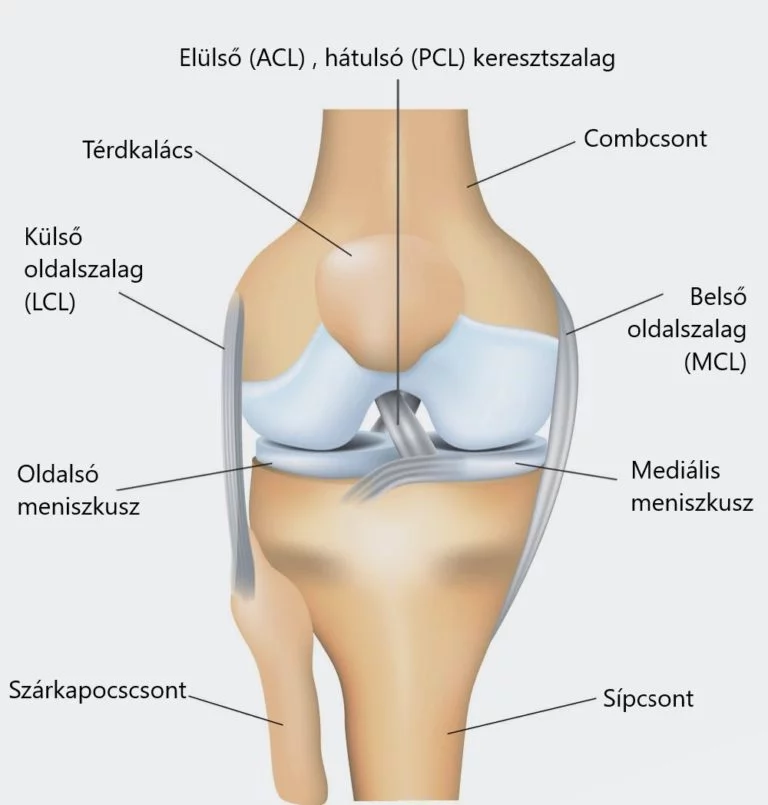

A térd egy összetett ízület, amely csontokból, inakból, szalagokból és izmokból áll. Ezek mind együtt dolgoznak a normál működés fenntartásán és a térd stabilitásának biztosításán. A térd a combcsont (femur), a sípcsont (tibia), és a patella (térdkalács) találkozásánál helyezkedik el.

A térd lehetővé teszi a láb hajlítását és nyújtását és mivel az emberi test súlyának nagy része ezen az ízületen keresztül oszlik el, ezért a jól működő, egészséges térd elengedhetetlen a mobilitásunkhoz. Mivel sok erőt és különféle intezitású mozgást visel, a térd könnyen sérülhet, például keresztszalag-szakadás vagy meniscus sérülés következhet be, különösen nagy erőkifejtés, például sportolás közben. A térd anatómiájának megértése javítja a térdproblémák specialistával történő megbeszélését és a megfelelő kezelési eljárás kiválasztását.

- Femur (combcsont): A test legnagyobb csontja, amely a térdízület felső részét alkotja.

- Tibia (sípcsont): A térd alatti csont, amely a súlyt hordozza.

- Fibula (szárkapocs csont): A tibia mellett fut, de nem vesz részt közvetlenül a térdízület működésében.

- Patella (térdkalács): Ez a kis, kerek csont védi az ízületet és segít a térd hajlításában.

A térdben található két porckorong (meniscus), amelyek egyfajta párnázó szerepet töltenek be. A belső és a külső meniscus segítenek elnyelni az ütéseket és stabilizálják a térdet.

Szalagok

- Elülső keresztszalag (LCA): Segít megakadályozni a sípcsont előre csúszását a combcsonton.

- Hátsó keresztszalag (LCP): Megakadályozza, hogy a sípcsont hátra csússzon.

- Mediális oldalszalag (MCL): Stabilizálja a térd belső oldalát.

- Laterális oldalszalag (LCL): Stabilizálja a térd külső oldalát.